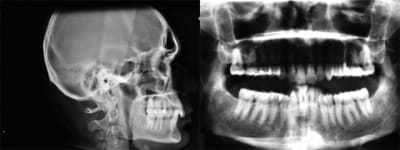

Départ

Depart 1 pohixz - Eugenol

Actuellement

et

je pense que dans 6 mois, j’aurai fini les dernières corrections

Actuellement 2 dilnlk - Eugenol